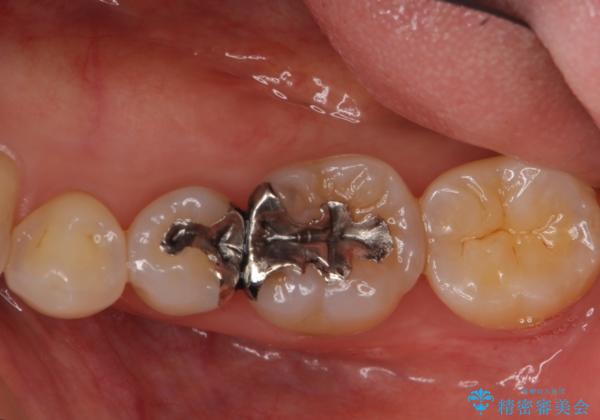

目立つ銀歯を全て白く セラミックで虫歯治療

- 銀の詰め物が気になるとのことで来院。

2本隣り合っているつめものを、同時にやりかえをしました。

- 14万円(左下5・左下6 emaxプレスインレー 7万円 x 2)費用は治療当時の料金となります

向かい合う銀歯を同時にやり変えることで、コンタクト(歯と歯の間の形)を理想的に仕上げることができ、ものも挟まりにくいように仕上げることができます。